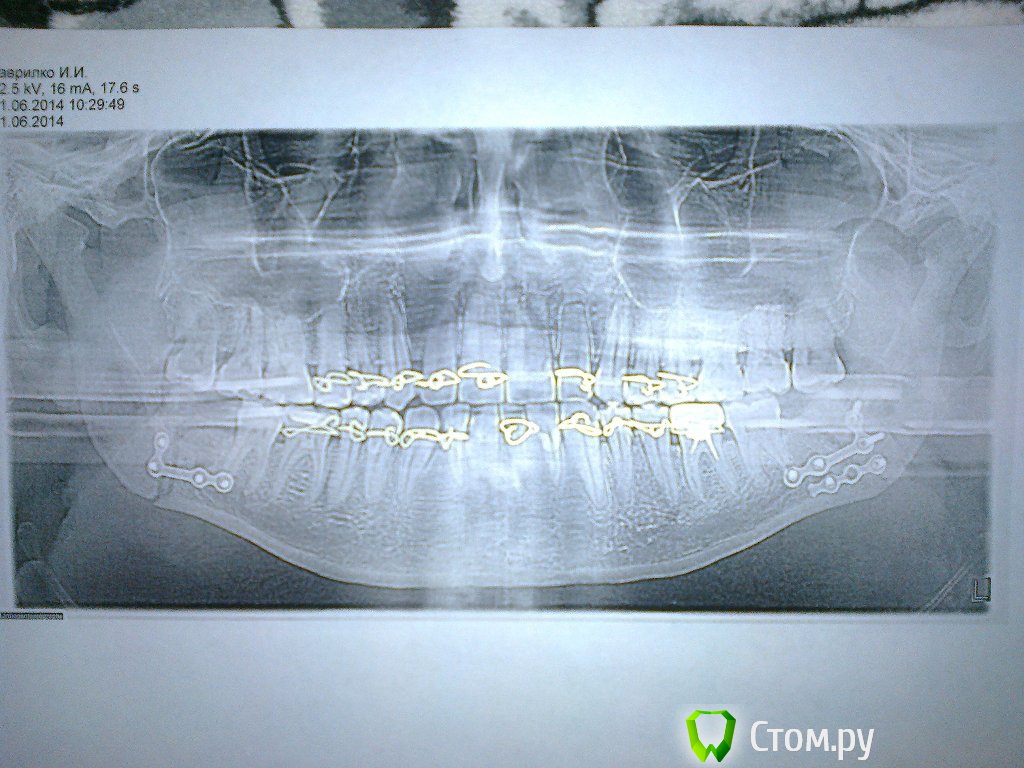

сирена Опубликовано 28 июня, 2014 Поделиться Опубликовано 28 июня, 2014 Пожалуйста! Помогите с моей ситуацией, ответьте, знающие люди!!!!!!!!!Лечение Вам проведено правильно,на втором снимке(после остеосинтеза минипластинами) отломки сопоставлены хорошо.Подвижность зубов лечить у пародонтолога,пока Вам необходимо очень тщательно соблюдать гигиену полости рта(чистить зубы после каждого приёма пищи мягкой зубной щёткой),можно дополнительно делать ванночки с настоем трав(шалфей,ромашка,календула) ,аппликации геля "Метрогил-дента" или "Холисал" на дёсны.Ограничение открывания рта это частое осложнение при переломах нижней челюсти,особенно ангулярных(как у Вас),надо разрабатывать.Перелом сложный,поэтому и реабилитация может быть длительной,наберитесь терпения.Нарушение прикуса - нехорошо,но без очного осмотра и снимков на настоящий момент никто Вам не сможет сказать ничего определённого.Более полную консультацию получите у своего лечащего врача - челюстно-лицевого хирурга,судя по всему,это опытный и грамотный врач."Ждал денег" это Ваши домыслы,извините.Кстати,остеосинтез минипластинами,по-моему,не входит в услуги по ОМС,это высококвалифицированная помощь. 3 Ссылка на комментарий

ivanich 82 Опубликовано 28 июня, 2014 Автор Поделиться Опубликовано 28 июня, 2014 Лечение Вам проведено правильно,на втором снимке(после остеосинтеза минипластинами) отломки сопоставлены хорошо.Подвижность зубов лечить у пародонтолога,пока Вам необходимо очень тщательно соблюдать гигиену полости рта(чистить зубы после каждого приёма пищи мягкой зубной щёткой),можно дополнительно делать ванночки с настоем трав(шалфей,ромашка,календула - 1 ст.ложка на стакан кипяч.воды),аппликации геля "Метрогил-дента" или "Холисал" на дёсны.Ограничение открывания рта это частое осложнение при переломах нижней челюсти,особенно ангулярных(как у Вас),надо разрабатывать.Перелом сложный,поэтому и реабилитация может быть длительной,наберитесь терпения.Нарушение прикуса - нехорошо,но без очного осмотра и снимков на настоящий момент никто Вам не сможет сказать ничего определённого.Более полную консультацию получите у своего лечащего врача - челюстно-лицевого хирурга,судя по всему,это опытный и грамотный врач."Ждал денег" это Ваши домыслы,извините.Кстати,остеосинтез минипластинами,по-моему,не входит в услуги по ОМС,это высококвалифицированная помощь.Спасибо большое за ответ, может я и не прав по поводу врача, остеосинтез минипластинами делали в окружной больнице г. Сургута ХМАО-Югра, в отделение ЧЛХ, со мной лежало много подобных больных и кому требовалось делали подобные операции в рамках ОМС. Просто в панику меня ввел врах - хирург, который дал 4 дня походить без резиновых тяг и на 5 день обещал снять шины, однако когда я к нему пришел, ему не понравился прикус, он сказал, что наверное плохо прикрепили минипластины и осталась какая-то подвижность и надо ехать на прием в Сургут к челюстно-лицевому хирургу и скорее всего придется делать повторную операцию. Представьте мое состояние, месяц еще не прошел с прошлой операции, здоровые зубы шатаются, нижняя часть лица онемевшая, два шрама на лице и вновь все резать??????!!!!!!!!! Вот почему решил попросить помощи у знающих врачей, то есть у Вас, люди. С ув. Иван. 1 Ссылка на комментарий

ivanich 82 Опубликовано 30 июня, 2014 Автор Поделиться Опубликовано 30 июня, 2014 Вот посмотрите снимки за 11.06. и за 23.06. Где за 23 немного дернулся при снимке, вот как по середине и съехала челюсть. Скажите, что по снимкам, все правильно сопоставлено и срастается? Ссылка на комментарий

Acidrocker Опубликовано 30 июня, 2014 Поделиться Опубликовано 30 июня, 2014 Вот посмотрите снимки за 11.06. и за 23.06. Где за 23 немного дернулся при снимке, вот как по середине и съехала челюсть. Скажите, что по снимкам, все правильно сопоставлено и срастается?По снимкам все сопоставлено замечательно. То, что посередине - дефект снимка. Ссылка на комментарий